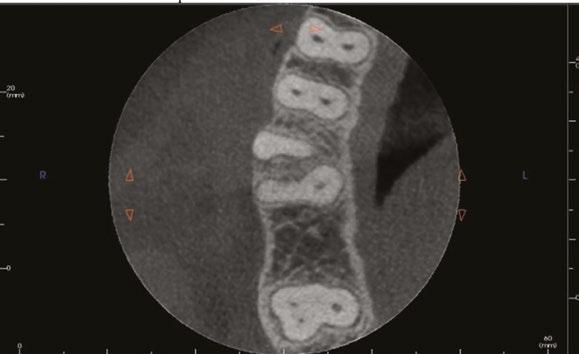

Figure 1: This CT reconstruction of the apical third of a premolar root shows the challenge we often encounter when negotiating root canals to their terminal lengths. In just these two canals, there are five potential impediments to passage of the first negotiating file to length